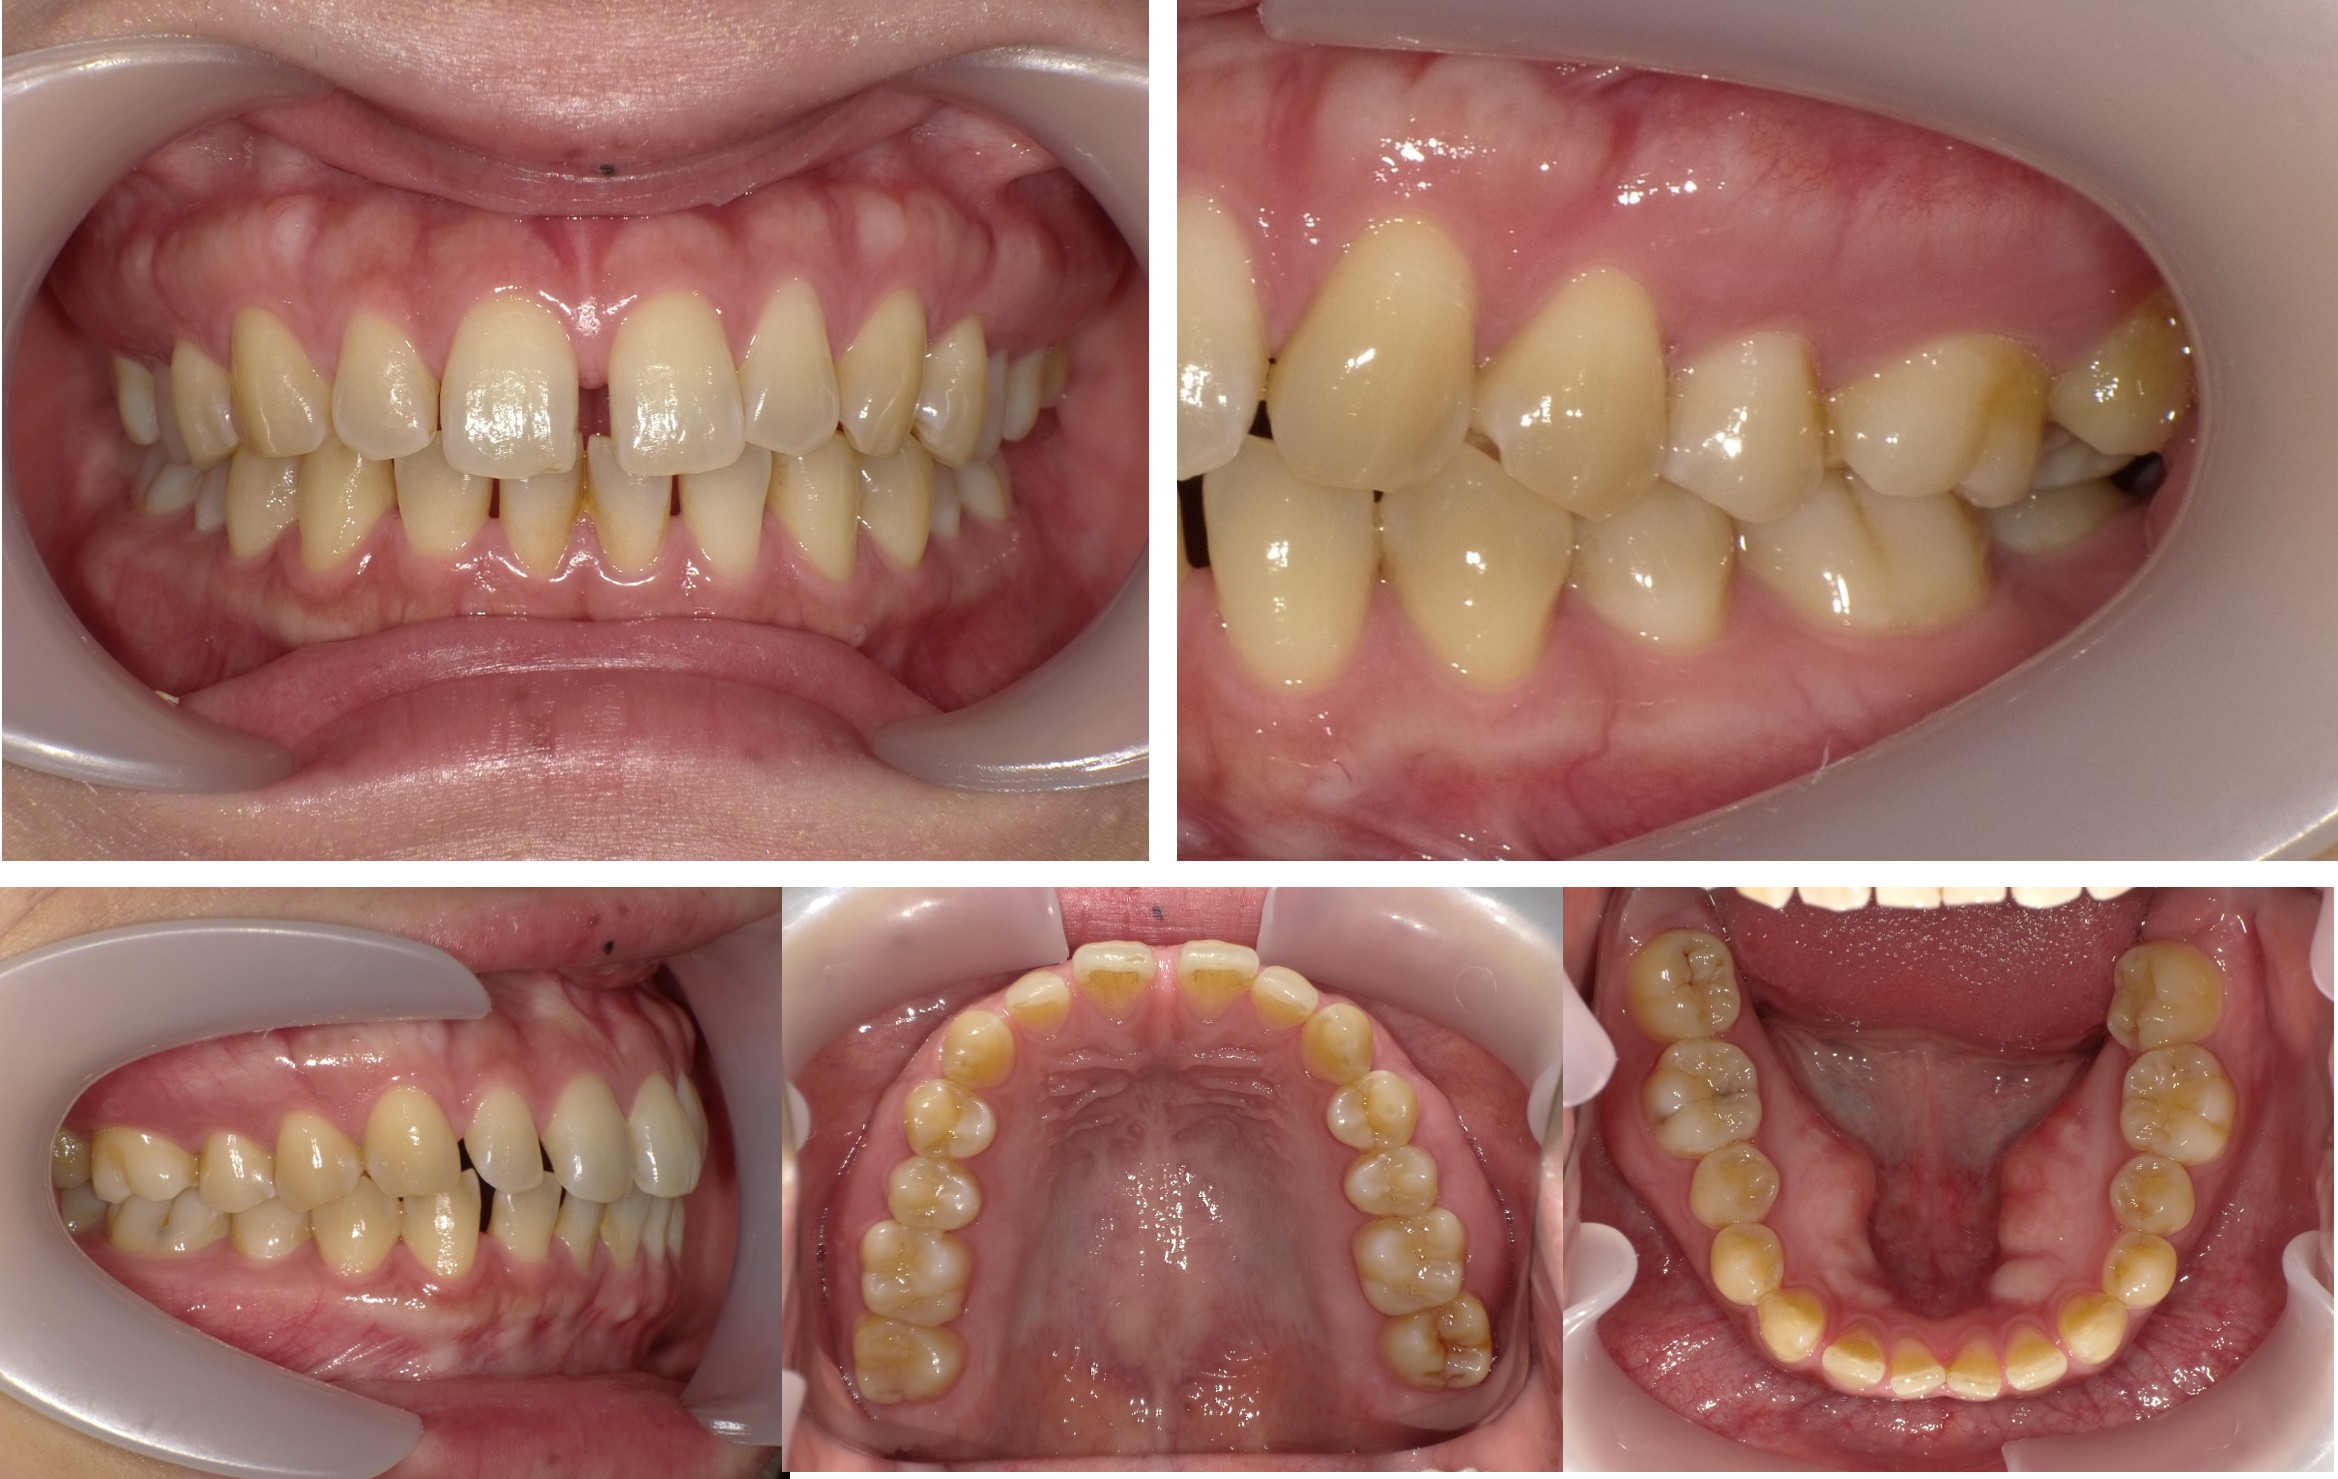

インビザライン矯正治療を終えて・・・

歯列矯正治療のビフォーアフター、治療にかかった期間や来院回数について解説いたします。

治療症例

歯列矯正治療にかかった期間、来院回数

■使用装置:インビザライン・アライナー(透明マウスピース型矯正装置)

■動的治療期間:8カ月

■保定治療期間:3年

■来院回数:8回 ※初診診察、コンサルテーションを含む